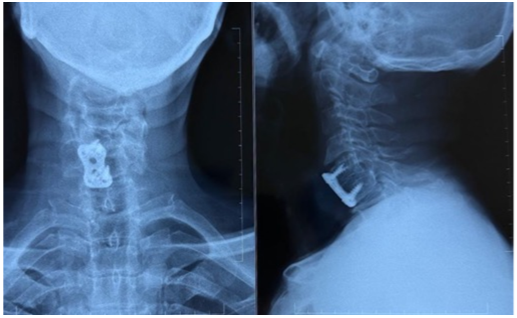

Fusion status was assessed at 6 months postoperatively (Fig. 5).

Figure 5: Radiograph on post-operative 6 months showing fusion in conventional plate anterior cervical discectomy and fusion and standalone polyetheretherketone cage.

In the ACP group, 13 out of 15 patients (86.67%) achieved arthrodesis, while in the PEEK cage group, 12 out of 14 patients (85.71%) achieved fusion. Statistically insignificant differences in fusion rates among the two groups (P = 1.00) were observed. Number of patients who did not achieve fusion by 6 months was small and comparable between groups: 2 patients (13.33%) in the plating group and 2 patients (14.29%) in the PEEK cage group.